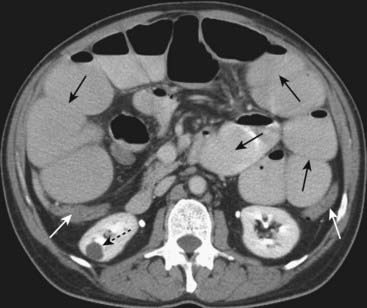

Figure 14-9 Small bowel obstruction, CT with oral and IV contrast.

There are multiple fluid- and contrast-filled, dilated loops of small bowel demonstrated (solid black arrows), while the colon is collapsed (solid white arrows), indicating a small bowel obstruction. Bowel wall enhancement or lack thereof may be obscured by oral contrast, a drawback to the use of oral contrast. Incidentally noted is a right renal cyst (dotted black arrow).